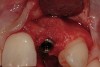

A 34-year-old woman presented with a chief complaint of mild discomfort and swelling associated with the maxillary left lateral incisor. The patient reported a history of root canal therapy and crown performed approximately 10 years earlier. Findings from the clinical examination revealed a localized buccal gingival swelling at the level of the mucogingival junction distal to the lateral incisor, with a 9-mm probing depth on the direct facial of the tooth (Figure 1 ). Observations from the radiographic examination demonstrated a periradicular radiolucency but suggested normal interdental bone levels (Figure 2 ). Surgical exposure following flap elevation exposed a 10-mm dehiscence defect of the buccal plate (Figure 3 ), which was consistent with a vertical root fracture and hopeless prognosis. The lateral incisor was extracted to minimize the loss of alveolar bone and this was followed by thorough degranulation of the socket. Particulate FDBA saturated with rhPDGF-BB for 10 minutes was then applied to augment the deficient ridge in preparation for future implant placement (Figure 4 ). The extraction site was developed to approximate the contours of the adjacent alveolar ridge. Then, a resorbable collagen membrane (Bio-Gide®, Osteohealth) was placed over the graft to facilitate graft containment and maintenance of desired alveolar contours (Figure 5 ). Placement of the membrane without disruption or displacement of the graft during completion of the surgical procedure and suturing is critical to ensure clot formation that will support bone formation.

Figure 1   Localized gingival erythema and swelling associated with maxillary left lateral incisor.

Figure 1